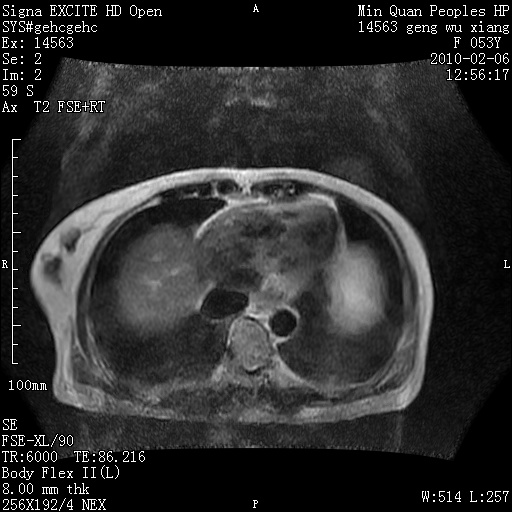

标题: MRI2762:胆道梗阻原因?

f,53y,全身黄染多日。

高位胆道梗阻 胆管癌可能性大

支持 高位胆道梗阻 胆管癌可能性大。